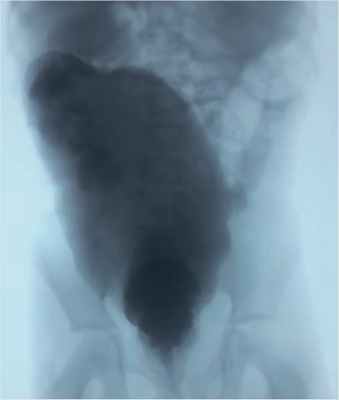

Под аппаратно-масочным наркозом было выполнено удаление калового камня. После подготовки ребенка курсом очистительных клизм и слабительных препаратов выполнена ирригография: сигмовидная и прямая кишка резко расширены в диаметре до 11 см (в прямой проекции), сигмовидная кишка удлинена с образованием дополнительной петли, гаустрация сглажена. Опорожнение неполное. После опорожнения в боковой проекции ампула прямой кишки расширена до 8,5 см, рельеф имеет грубую складчатость (рис. 2).

Рисунок 2. Ирригография перед повторной аноректопластикой